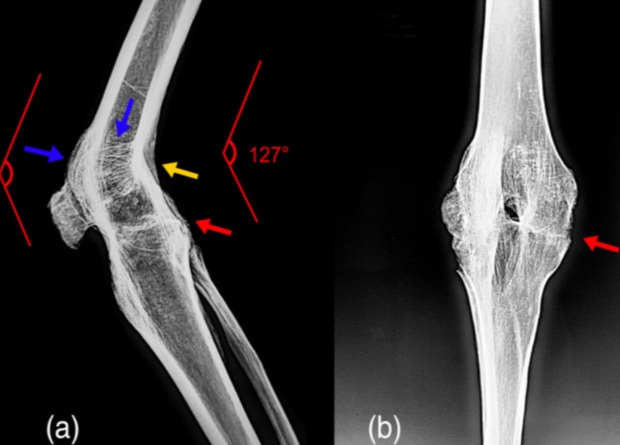

Палеопатологи исследовали останки кочевника, захороненного в Синьцзяне около 542–391 годов до нашей эры. Они обнаружили у него ряд патологий, среди которых выделяется анкилоз коленного сустава. Похоже, он развился за несколько лет до смерти из-за септического артрита, вызванного разрывом связки. Результаты исследования опубликованы в International Journal of Osteoarchaeology.

Анкилоз представляет собой неподвижность сустава, которая возникает из-за сращивания суставных концов сочленяющихся костей или разрастания фиброзной ткани. Как правило, эта патология развивается вследствие травм и заболеваний, хотя иногда носит врожденный характер из-за артрогрипоза. Чаще всего анкилоз развивается на нижних конечностей. Так, самой распространенной формой выступает анкилоз коленного сустава (порядка 50 процентов случаев).

Анкилоз коленного сустава известен и в археологическом контексте. По всей видимости, самым известным примером служат останки отца Александра Македонского — царя Филиппа II, который за три года до его убийства в 336 году до нашей эры получил ранение копьем в ногу, оставившее его хромым из-за развития анкилоза. Похожую патологию ученые обнаружили на останках женщины 36–45 лет, погребенной в английском средневековом некрополе около 1250–1400 годов. Известны такие останки и в Китае, где в ходе раскопок в Синьцзяне археологи нашли останки мужчины 50–65